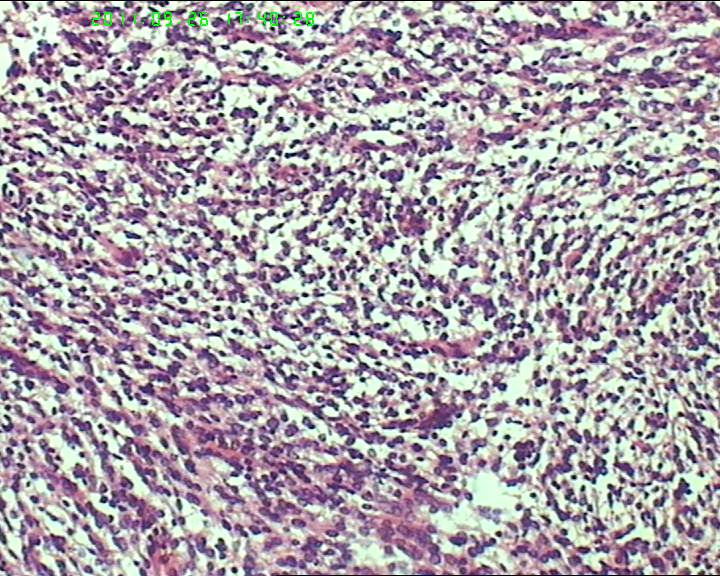

包块与大网膜粘连,根部附着于肠系膜,脾曲处有较多积血块 但无活动性出血,肠系膜上有较多粟粒样结节,白色质韧。与子宫 输卵管 卵巢没有关系.

灰白不整形肿物一个,大小18*15*9cm,表面结节状,包膜完整,切面灰白,中央可见坏死区,质软,范围5*4cm。其余切面多彩 部分半透明状 质中。

鉴别诊断排排队:1、GIST,2、MPNST,3、去分化脂肪肉瘤,4、恶性间皮瘤,5、恶性SFT,6、平肉

主要考虑前二者。CD34,CD117,S-100,BCL-2,SMA, D2-40,CR, VIM. 结果如何?请楼主揭谜底吧。